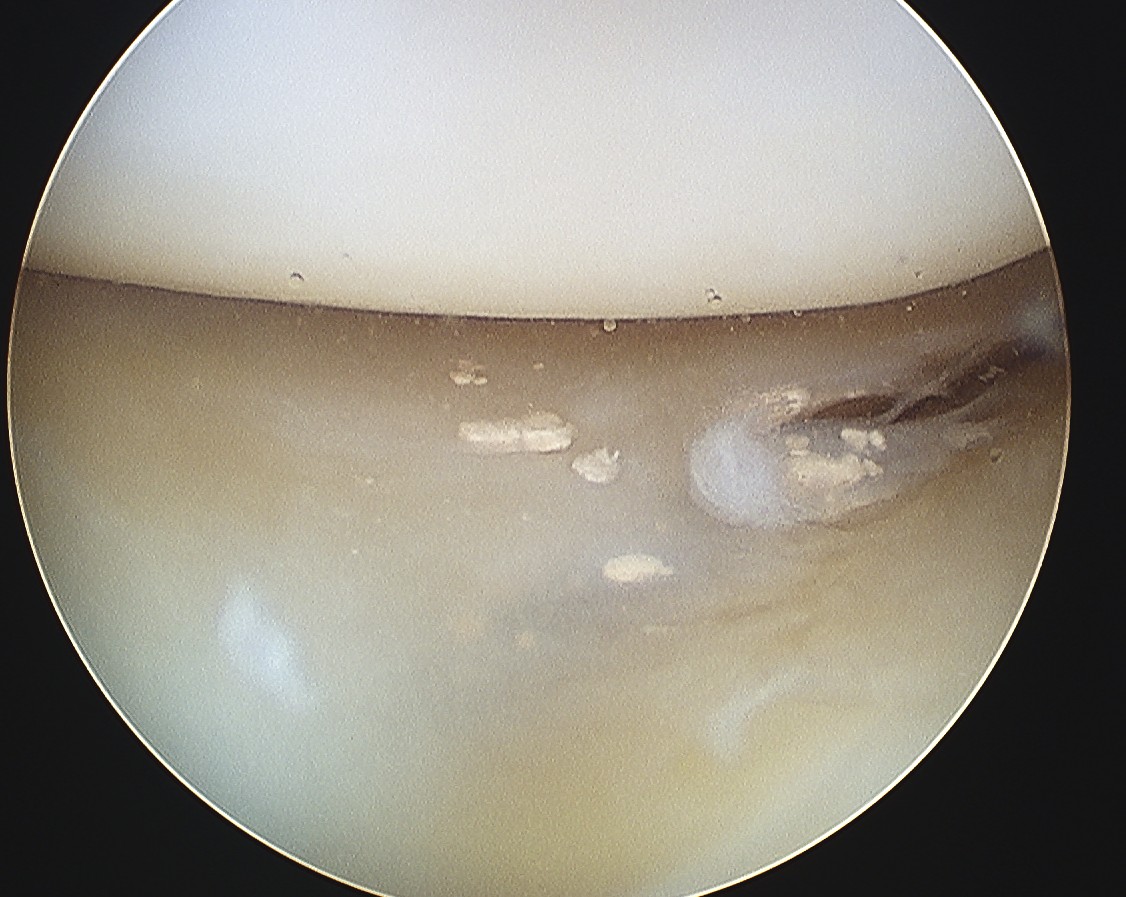

- crystals of Monosodium Urate in synovial fluid

- tophi ("Porous stone") urate in soft tissues